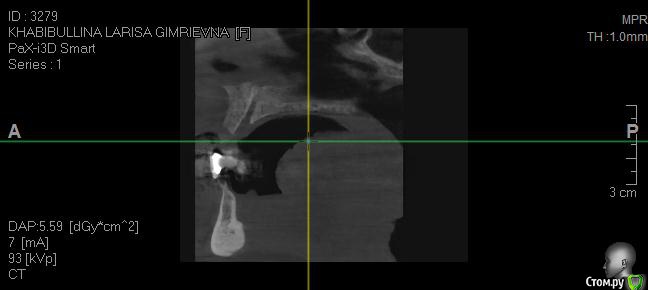

Реальная картина на сегодня:

- Нижняя челюсть выдвинулась в перед (возрастной мезиальный прикус)

- Нижняя челюсть гипермобильна , дисфункция ВНЧС, хрустит прикус прогенически,  (диагноз ЧЯХ (в лечение отказан) Рот открывается рывком (безболезненно)

1. Сильно выдвинулась челюсть. Вопрос – можно ли с помощью имплантации (с несъемной конструкцией) исправить прикус и остановить процесс выдвижение нижней челюсти.

2. Достаточно ли кости для проведение имплантации? Нужна ли ринопластика?

5. Если имплантанты на верхней челюсти будут установлены под определенным углом, не скажется ли это негативно на прочности конструкции?  Достаточно ли 6 имплантантов на верхнюю челюсть?